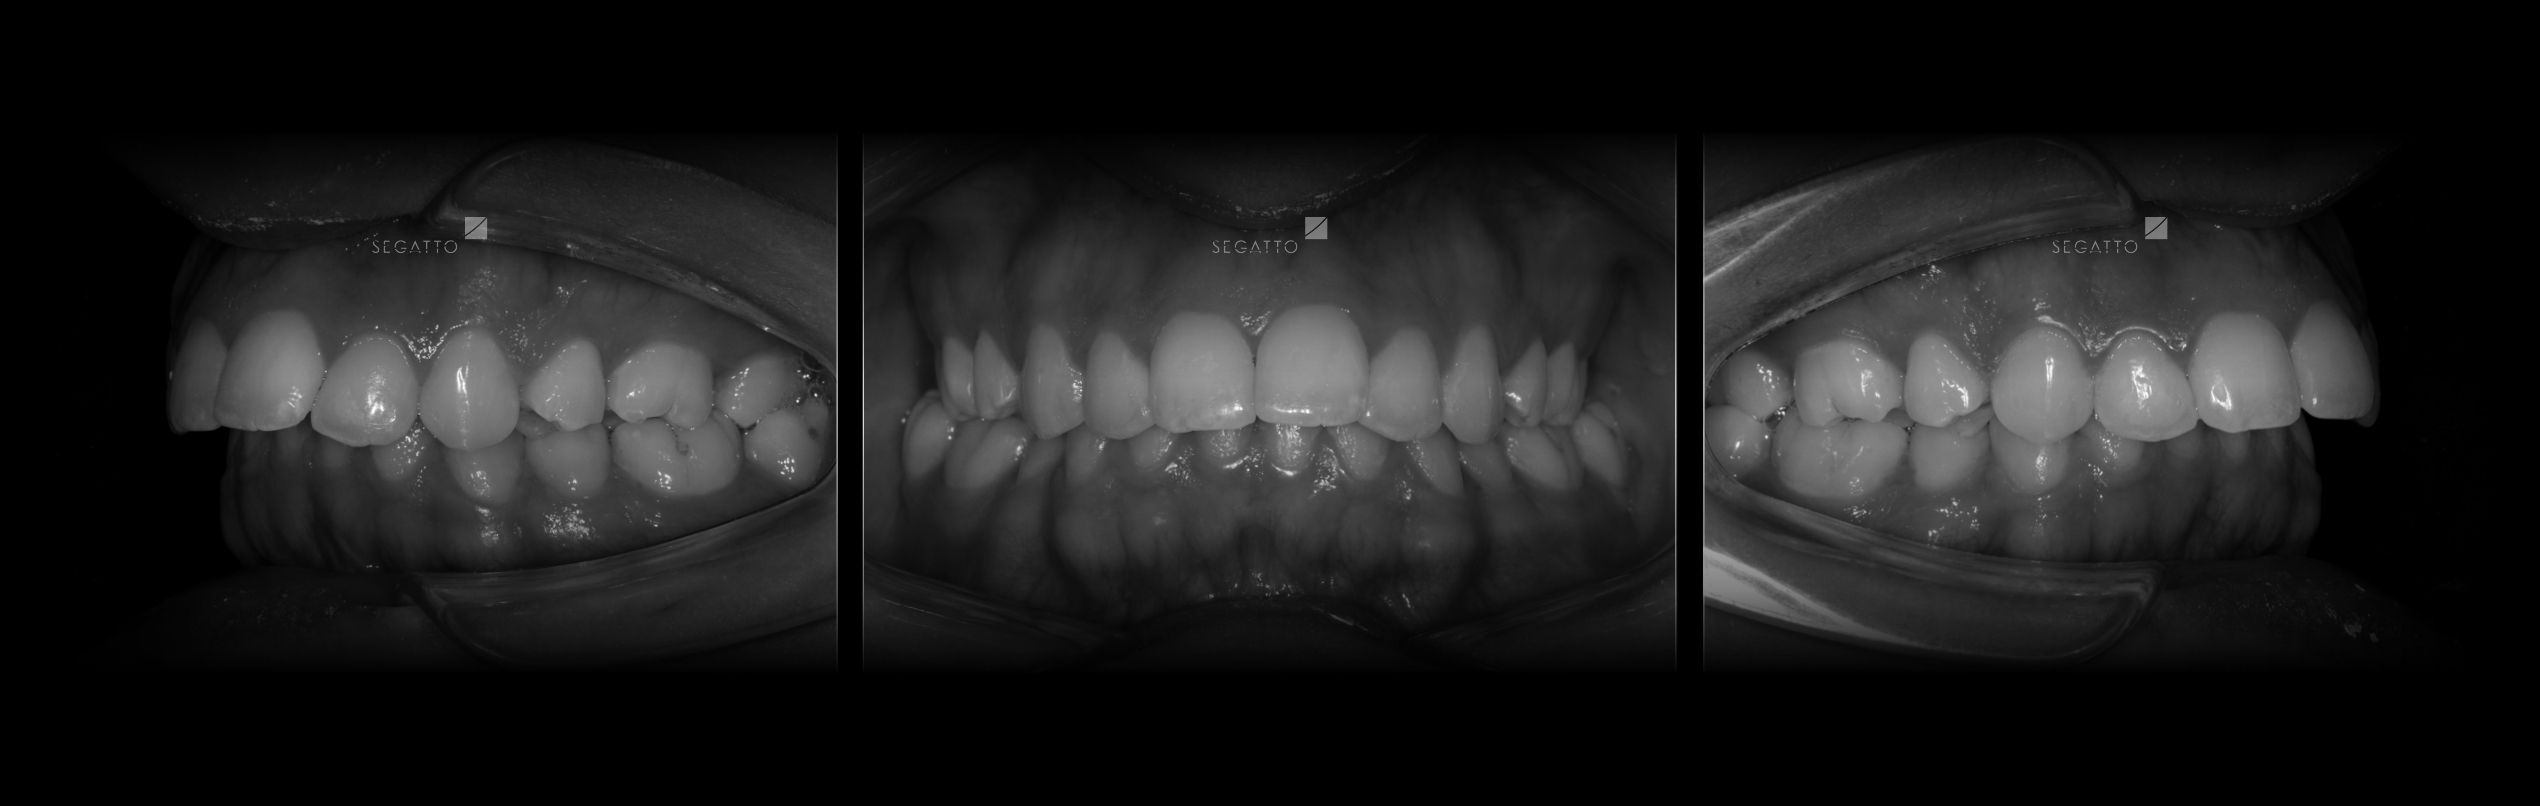

Orthodontics

Cases